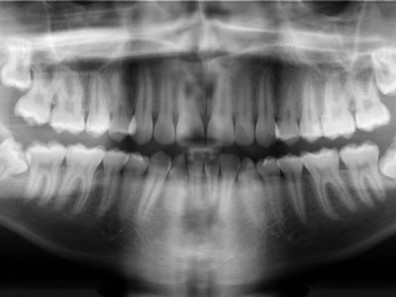

Técnica que produz uma única imagem tomográfica das estruturas faciais que inclui ambos os arcos dentários, maxilar e mandibular, e suas estruturas de suporte. A imagem produzida é das mais úteis para diagnóstico e avaliação por proporcionar ampla visualização dos maxilares.